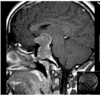

En 41-årig kvinde har fået foretaget en MR-skanning af hypofysen (se billede).

Hvilken akut blodprøve vil du bestille på KBF?

a. Kortisol

b. Prolaktin

c. ACTH

d. TSH

e. IGF1

*b. Prolaktin